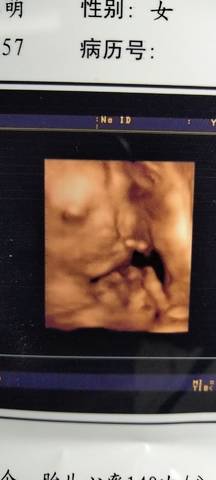

四维彩超比传统B超好?医生:以后别再花冤枉钱了!

你可能听说过一种说法:做大排畸筛查,做四维彩超比做B超更准。其实,这种说法是不准确的,而且医生在实际...

四维彩超虽然好,但还可能造成伤害

所以高龄准妈妈们除了做好常规的检查,要尤其重视彩超检查(三维彩超、四维彩超),以便更准确地了解胎宝宝...